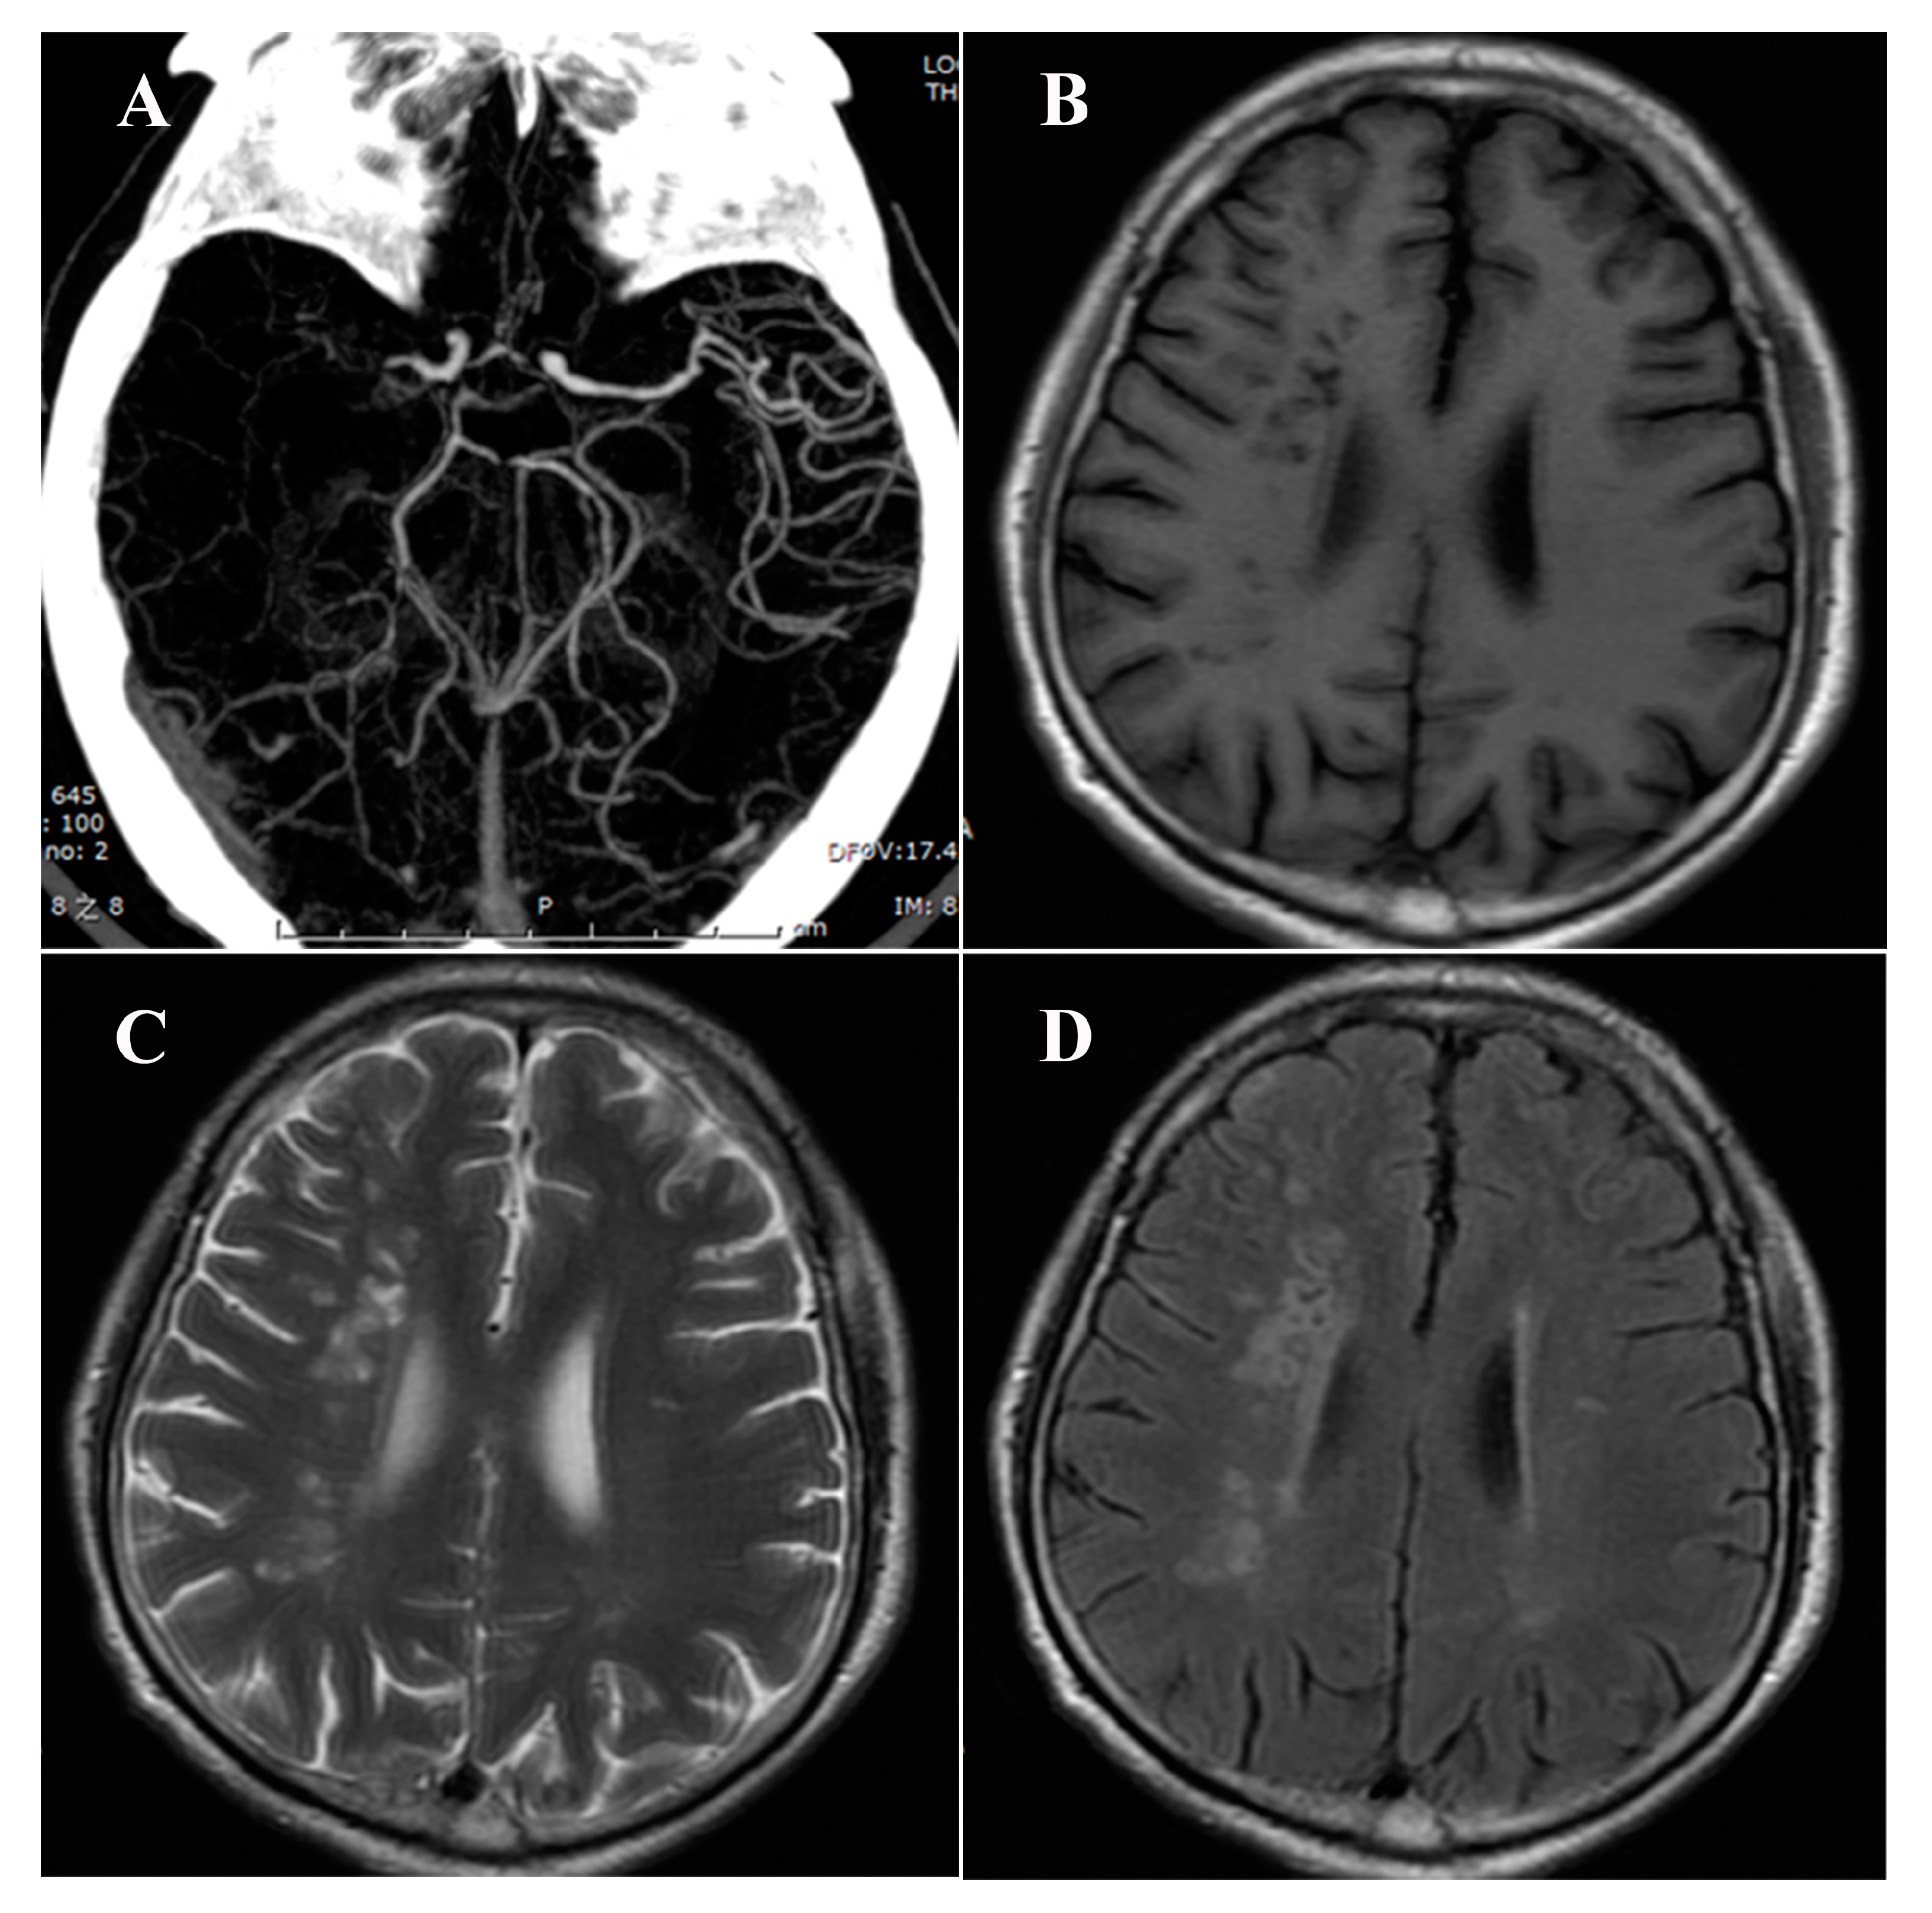

| Lacunae | |||

| Presence of lacunae, n (%) | 55 (25.1%) | 95 (43.4%) | <0.001 |

| Two or more lacunae, n (%) | 21 (9.6%) | 43 (29.7%) | <0.001 |

| No. of lacunae, median (IQR) | 0 (0~1) | 0 (0~2) | <0.001 |